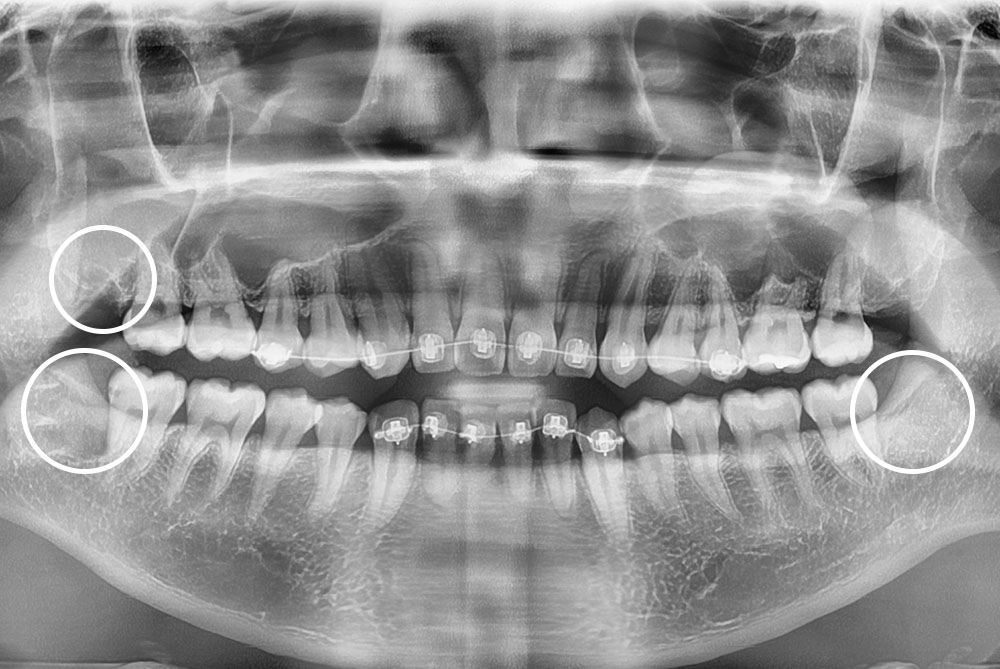

[사랑니] 매복 사랑니 발치

치료후 : 2021-10-07

세종치과는 구강악안면외과학 박사이신 원장님이 발치하는 치과입니다.